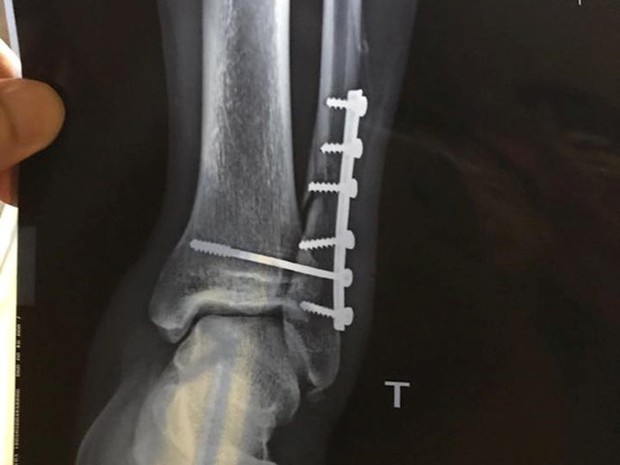

Sau ca phẫu thuật đầu tiên, cổ chân trái của Dương Văn Hào đã được cố định bằng 6 chiếc đinh.

6 cái đinh đã được thắng vào cổ chân của tiền vệ này. Từ một tài năng triển vọng, người đã từng tham gia U20 World Cup 2017 cùng đội U20 Việt Nam, tương lai của Dương Văn Hào đã trở nên mờ nhạt. Không chỉ có xương gãy, mà cả khớp và dây chằng cổ chân trái của cầu thủ này cũng bị tổn thương nghiêm trọng.

Cần phải tiến hành thêm 3 cuộc phẫu thuật để đi cắm đinh, sau đó thực hiện 1 năm tập vật lý trị liệu và thi đấu ở giải hạng Ba cùng đội trẻ Viettel, Dương Văn Hào đã từ từ trở lại với sự nghiệp bóng đá chuyên nghiệp. Chấn thương kinh hoàng đã không thể khuất phục ý chí của chàng trai quê Thái Nguyên. Anh đã kiên nhẫn tập luyện, đợi ngày được trở lại với đội một Viettel.